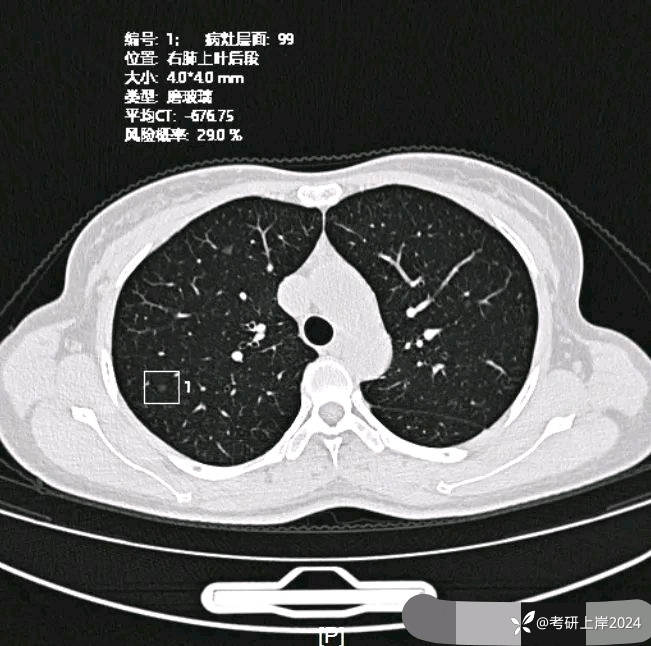

患者最近的检查有AI辅助诊断意见,找出的病灶分别如下:

病灶8:右上叶微小磨玻璃结节,轮廓较清,考虑肺泡上皮增生可能性较大;